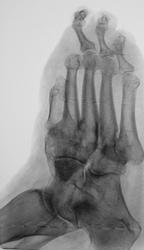

Пол пациента: Женский пол Тип патологии: Другое Область исследования: Скелетно-мышечная система Методы исследования: Rg Пациент направлен на рентгенографию стопы. https://radiomed.ru/sites/default/files/styles/case_slider_image/public/user/12/2.dscn0864.jpg?itok=uzT7C77w ID:25515 Чт, 10/01/2013 - 22:56 #1 Наталия Васильевна Не на сайте Был на сайте: 5 лет 10 месяцев назад Зарегистрирован: 25.09.2011 - 09:02 Публикации: 754 Диабетическая стопа? Состояние после ампутации 1-2 пальцев, остеомиелит с разрушением костей предплюсны. А что в анамнезе? Чт, 10/01/2013 - 23:15 #2 Катенёв Валенти... Не на сайте Был на сайте: 7 лет 2 месяцев назад Зарегистрирован: 22.03.2008 - 22:15 Публикации: 54876 В анамнезе диабет. Пт, 11/01/2013 - 12:14 #3 Popovpavel Не на сайте Был на сайте: 7 лет 4 месяцев назад Зарегистрирован: 08.06.2009 - 00:23 Публикации: 649 Мощный лизис. Пт, 11/01/2013 - 19:03 #4 Наталия Васильевна Не на сайте Был на сайте: 5 лет 10 месяцев назад Зарегистрирован: 25.09.2011 - 09:02 Публикации: 754 А дальше-выше, выше и выше. Очень неблагодарное лечение.

Диабетическая стопа? Состояние после ампутации 1-2 пальцев, остеомиелит с разрушением костей предплюсны. А что в анамнезе?

В анамнезе диабет.

Мощный лизис.